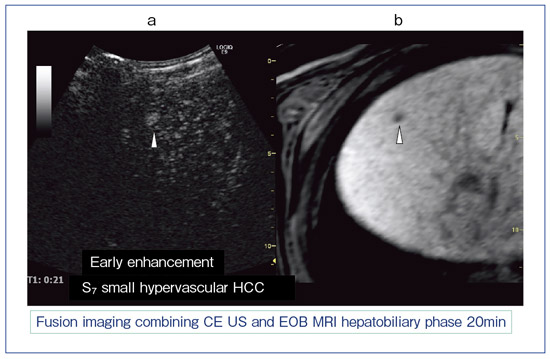

フィリップス、「Liver Fat Quantification(肝脂肪化定量評価。肝臓がん|消化器|診療内容|医療法人 甘木第一クリニック。肝臓がん|消化器|診療内容|医療法人 甘木第一クリニック。sakuraさん専用 蔵王吊るし柿4kg 紅干し柿 600g。Contrast Enhanced Ultrasound (CEUS) | フィリップスヘルスケア。Liver Ultrasonography | SpringerLink。キヤノンメディカルシステムズ、『肝臓の脂肪量の汎用超音波画像。Imaging Features of Hepatocellular Carcinoma in the Non。Imaging Features of Hepatocellular Carcinoma in the Non。714cFtk9QyL._AC_UF350,。肝臓病変における超音波の最新情報-第24回腹部放射線研究会。KMS_M01_XXX_670.jpg。腹部の超音波検査健康なヒト胆嚢 - 胆嚢のストックフォトや画像。